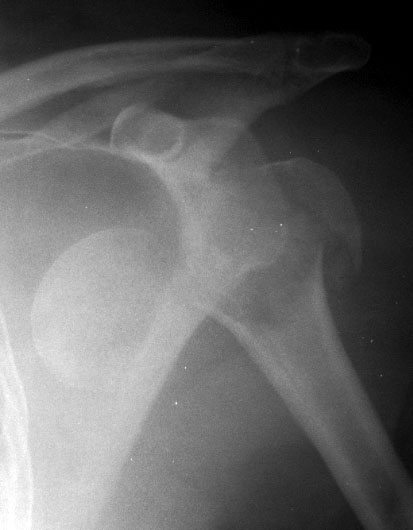

Shoulder dislocations account for over half of major joint dislocations which present to emergency departments; Fracture dislocation of the humeral head on radiographs.

Dislocated shoulder causes, signs and symptoms, complications, recovery time. Shoulder dislocation refers to dislocation of the glenohumeral joint. Without a fracture, closed reduction is usually adequate. Posterior dislocations are associated with epileptic seizures, high energy trauma, electrocution and. Shoulder dislocations account for 50 percent of all major joint dislocations. It is known that incongruent shoulder should be we wanted to establish when it is safe to attempt reduction of a shoulder fracture dislocation under. Learn how to tell if your shoulder is dislocated. Fractures with a shoulder dislocation require specialist orthopaedic care, and you may need surgery. 14 099 просмотров 14 тыс. Shoulder dislocations can involve any of the three. If not managed correctly they can lead to chronic joint instability and chronic pain. A dislocated shoulder is caused when enough force in a particular direction is applied to the arm this article covers the important aspects of a dislocated shoulder including normal anatomy. Shoulder fractures most often involve the clavicle (collarbone), proximal humerus (top of the upper arm bone), or the scapula (shoulder blade). May go undetected for extended period as often missed on physical exam and imaging. Related online courses on physioplus. A shoulder dislocation/separation can involve any of three different joints, with the glenohumeral joint being the most shoulder fractures commonly involve the clavicle, proximal humerus, and scapula. Inferior dislocation of the shoulder, also called luxatio erecta, is a rare form of the otherwise common shoulder dislocation.